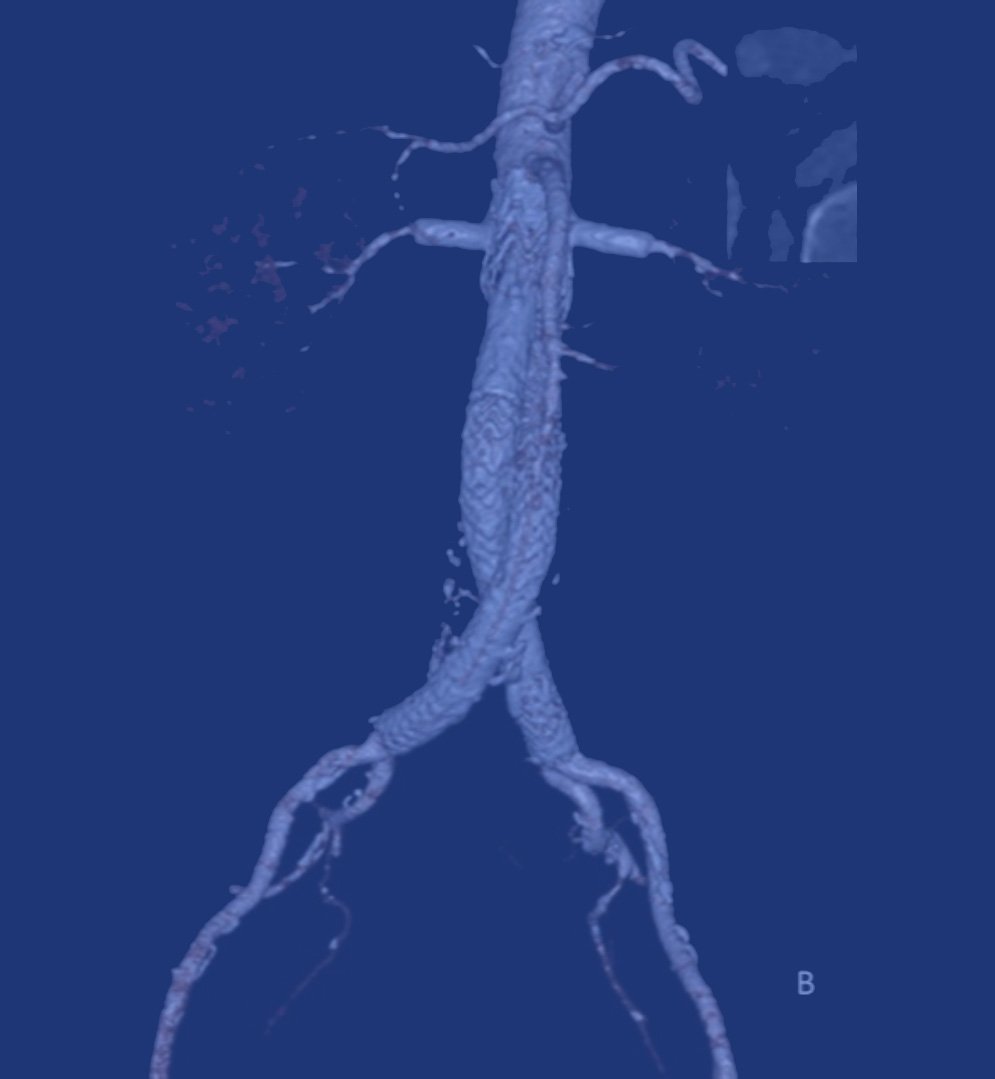

- Ενδαγγειακή αποκατάσταση (EVAR/TEVAR): με τοποθέτηση καλυμμένου μοσχεύματος (stent graft) μέσω μηριαίας προσπέλασης.

Ποια είναι τα πλεονεκτήματα της ενδαγγειακής μεθόδου (EVAR);

- Ελάχιστα επεμβατική.

- Σημαντικά μικρότερη νοσηλεία και ταχύτερη ανάρρωση.

- Χαμηλότερα ποσοστά περιεγχειρητικής θνητότητας.

- Απαιτεί όμως συστηματική παρακολούθηση για έλεγχο πιθανών ενδοδιαφυγών (endoleaks).

Ποιες είναι οι διαθέσιμες ενδαγγειακές τεχνικές για επιπλεγμένα ανευρύσματα;

- Fenestrated EVAR (FEVAR): χρήση μοσχεύματος με ειδικά ανοίγματα (fenestrations) για τα νεφρικά ή άλλες αρτηρίες.

- Branched EVAR (BEVAR): μοσχεύματα με έτοιμους κλάδους για ανακατασκευή σπλαχνικών αγγείων.

- Chimney ή snorkel techniques: παράλληλη τοποθέτηση stents σε ζωτικά αγγεία για διατήρηση βατότητας.